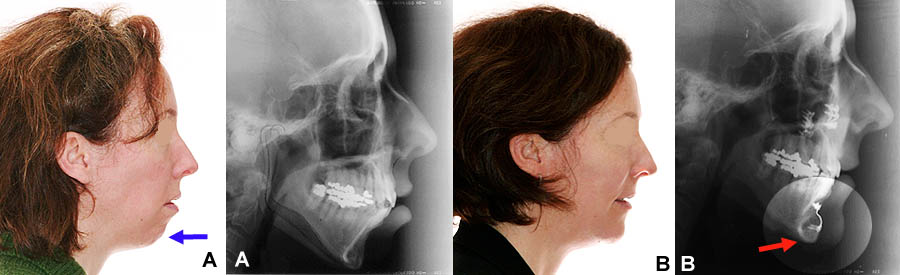

Chirurgie orthognathique multiple (A) Femme de 45 ans avec un menton reculé. La mâchoire supérieure a été “remontée” (impaction maxillaire) et le menton a été avancé (génioplastie) pour donner plus de volume et améliorer le profil. (B) La plaque et les vis chirurgicales de rétention du menton (flèche), ainsi que les vis à la mâchoire supérieure, sont visibles sur la radiographie post-opératoire.